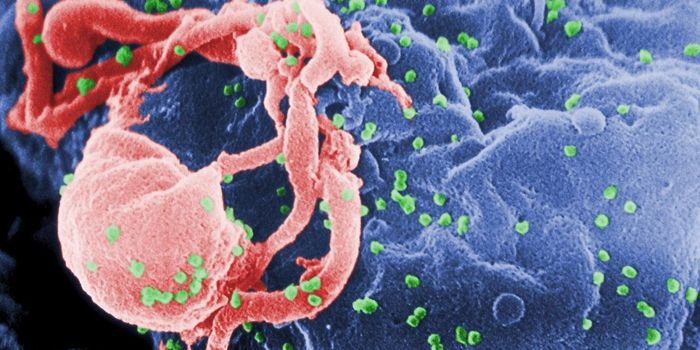

AUG 24, 2020ImmunologyOnce in the body, HIV tracks down T cells that bear the CD4 receptor. It attaches to these immune cells, fusing itself w ...

NOV 17, 2020ImmunologyLast year, around 1.7 million people became infected with HIV, with around half of these being women. Encouraging result ...

AUG 14, 2022ImmunologyFor the second time this year and only the fourth time ever, researchers have announced that a person has been cured of ...

APR 05, 2016Health & MedicineIn an effort to understand how HIV evolves resistance to drugs, scientists have found that it may be possible to steer t ...

MAY 23, 2024MicrobiologyWhen human immunodeficiency virus (HIV) emerged and was identified as the cause of acquired immunodeficiency syndrome (A ...

FEB 17, 2020ImmunologyYears of work and over $100 million in study costs have been abandoned after an HIV-vaccine tested in South Africa faile ...

JUN 04, 2016Clinical & Molecular DXA new study report found that at least 2,234 people contracted the human immunodeficiency virus (HIV) from blood transfu ...

JUL 10, 2020Drug Discovery & DevelopmentPharmaceutical company ViiV Healthcare has announced that its long-lasting, injectable drug, cabotegravir, is more effec ...